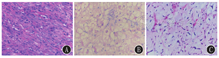

本组21例中,13例患儿行心脏肿瘤的完全切除或部分切除术[横纹肌瘤(图1A、图2A、图3A)4例、黏液瘤(图1B、图2B、图3B)3例、纤维瘤3例、炎性肌纤维母细胞瘤(IMT)(图1C、图2C、图3C)2例、畸胎瘤1例],围术期无死亡。术后随访3个月~7年,3例再次复发,其中2例黏液瘤患儿分别于术后1、3年出现肿瘤复发,均行二次手术切除治疗,术后随访5个月~1年无复发;1例IMT患儿,术中探查肿瘤浸润右心房及冠状动脉壁,行肿瘤部分切除术,术后予克拉霉素抗炎治疗2个月,术后1周残余肿瘤迅速增大,术后1个月肿瘤大小趋于稳定,术后10个月复查肿瘤消失。